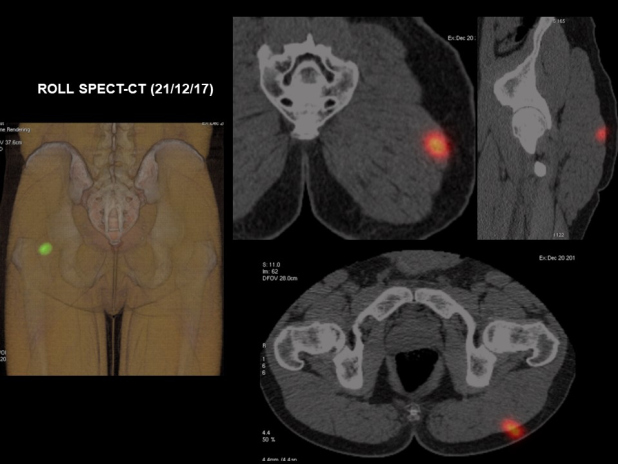

El 21/12/17 se procede a linfadenectomía inguinal izquierda por metástasis ganglionar de melanoma y biopsia/resección de lesión muscular en glúteo izquierdo mediante técnica ROLL guiada por SPECT-CT y ecografía (Fig. 6). El diagnóstico anatomopatológico corresponde a ganglios linfáticos (linfadenectomía inguinal superficial izquierda) con metástasis de melanoma en uno de seis, con extensión extracapsular. El fragmento remitido de músculo estriado (glúteo) se encuentra metastatizado por una neoplasia melánica maligna. No existe afectación de bordes quirúrgicos de resección. El perfil inmunohistoquímico es compatible con metástasis de melanoma. La lesión tumoral es positiva con HMB45 y S100.